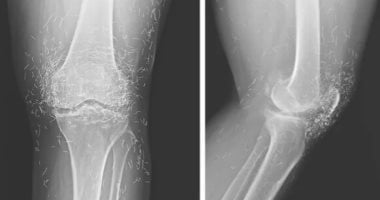

أظهرت الأشعة السينية لمريضة كورية جنوبية تبلغ من العمر 65 عامًا وجود مئات الخيوط الذهبية الدقيقة داخل مفاصل ركبتيها، وذلك بعد أن قصدت المستشفى تشكو آلامًا حادة ومتكررة في ركبتيها.

أشار الأطباء إلى وجود مئات النقاط الصغيرة اللامعة حول مفصل الركبة في الصور، وتبيّن لاحقًا أنها بقايا الخيوط الذهبية. كما أظهرت الصور زيادة في سماكة العظام ونمو نتوءات بجانب المفصل، وهي علامات تقدم التهاب المفاصل.

الأطباء يشيرون أيضًا إلى أن وجود هذه الخيوط قد يعيق التشخيص، إذ تسبب ظلالًا على صور الأشعة وتكون خطرًا عند الحاجة إلى إجراء تصوير بالرنين المغناطيسي بسبب احتمال التفاعل مع المجالات المغناطيسية القوية وما قد يترتب عليه من مخاطر صحية. وعلى الرغم من أن الأطباء لم يوضحوا ما إذا جرى استخراج الخيوط من ركبة المريضة، فإن بعض الحالات المشابهة تُترك الخيوط في مكانها ما لم تسبب مضاعفات مباشرة، لكن وجودها قد يؤدي أحيانًا إلى تكون أكياس أو التهابات يصعب علاجها.